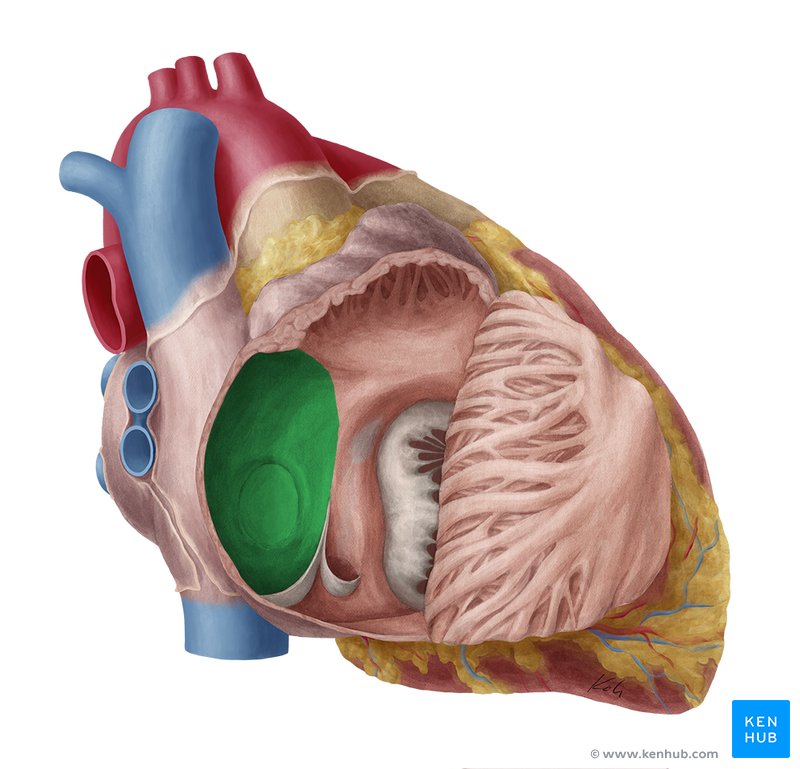

Left Atrium

Right Atrium

Left Ventricle

Right Ventricle

Tricuspid Valve

Bicuspid Valve

Aortic Valve

Papillary Muscle

Pulmonary Valve

Interventricular Septum

Chordae Tendineae